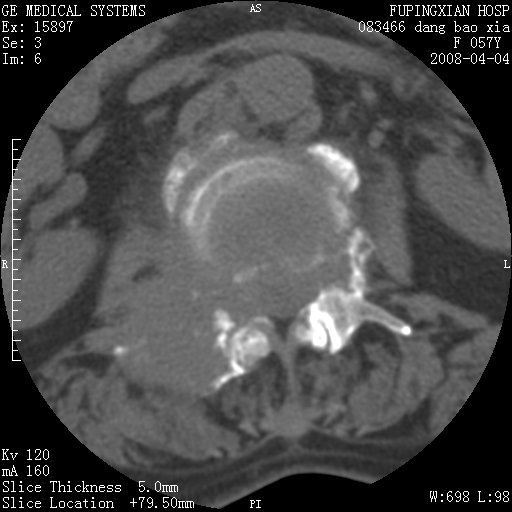

标题: CT12677:女性,57岁,疼痛数月。 [打印本页]

标题: CT12677:女性,57岁,疼痛数月。

椎体及附件骨质破坏同时伴软组织肿块,首先考虑恶性肿瘤。

骨组织起源,膨胀,软组织肿块=恶性改变:首选骨巨,其次转移瘤,再次脊索瘤

椎体及附件骨质破坏,伴软组织肿块,首先考虑恶性,不排除转移瘤.

椎体及附件溶骨性破坏,周围巨大软组织肿块,首先考虑转移瘤。